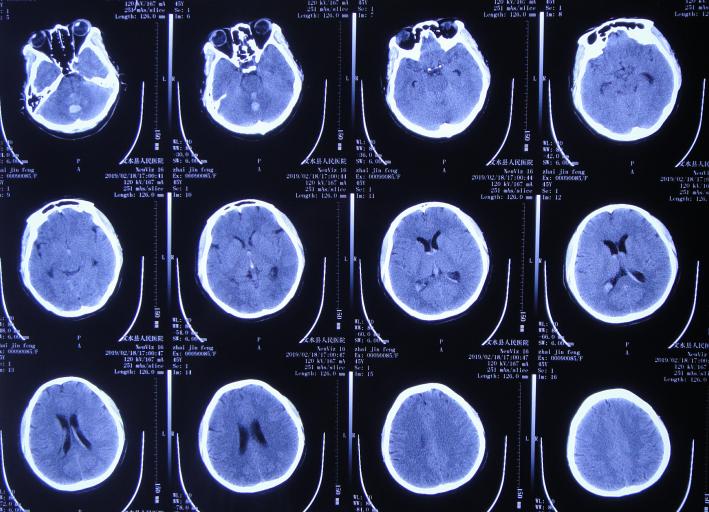

患者2019年2月18日下午,睡觉时突然出现剧烈头痛,持续无缓解,于是就诊于当地的山西省文水县某医院,查头颅CT示小脑出血破入脑室( 图-1 );考虑出血量不多,住院保守治疗。

图-1: 2019年2月18日头颅CT